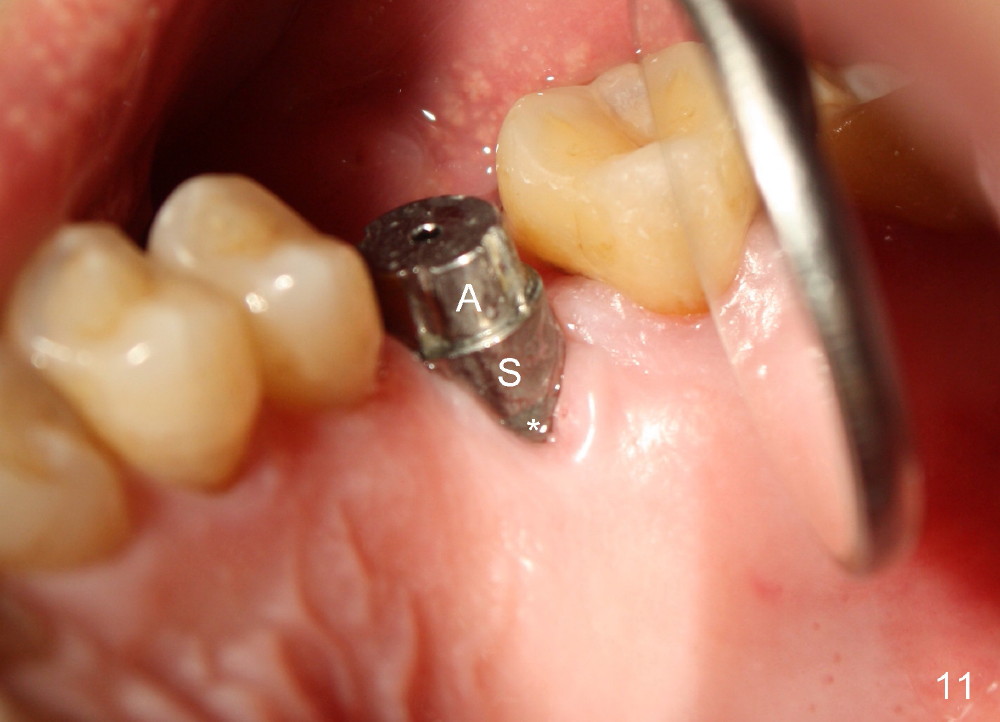

PA taken 3 months postop (Fig.9) shows bone graft in the mesial gap (*). Clinically the implant surface is less exposed buccally (Fig.10) than palatally (Fig.11 *).